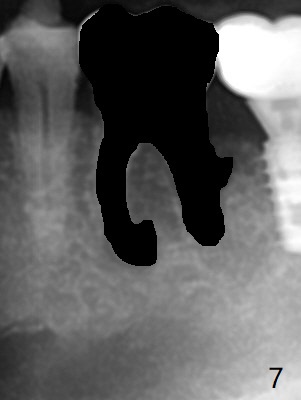

Venopuncture is conducted (Fig.1) for PRF and sticky bone (cortical chip and .5 cc ß-TCP). After use of proximators at #19, cowhorn forceps are applied, resulting in metal crown dislodgement. Since there is distal bone loss, distal socket sheath is contemplated. The tooth is sectioned. When an elevator is inserted between the roots, the distal root is loosened first. The 2 roots are removed, revealing a rounded end septum (Fig.2 S) and a larger distal socket. To avoid osteotomy deviation over the septum, a 12 mm bone trimmer is used, followed by point drill (Fig.3 *). But the lower half of the implant is deviated mesial (Fig.4) with decreased torque (~ 10 Ncm). To overcome this misfortune, the roots should not be removed until osteotomy is finished. Dual zones of bone graft is conducted. Sticky bone is placed until the plateau of the implant with a healing screw in place (Fig.4 * (bone zone)). After placement of a pair abutment, the same bone graft is packed until the margin of the abutment (Fig.5 * (soft tissue zone)). An immediate provisional is fabricated to close the socket with a piece of PRF as well. Fig.6-11 explains why the lower half of the implant deviates to the mesial socket, while Fig.12-16 illustrates how to prevent the deviation. After extraction of #19 (Fig.6,7), the crest of the septum is flattened (Fig.8 arrowhead) to prevent the initial deviation (Fig.9 red line). When a drill reaches a space (a socket, mesial in this case), the drill is deflected to the least resistant area (Fig.10 a bent red line), leading to the implant deviation apically (Fig.11 green). To prevent the apical deviation, therefore, the roots of the affected tooth is temporarily not removed (Fig.12). The osteotomy should not deviates with surgical guide because of similar density between the tooth and the bone (Fig.13). When the osteotomy is finished (Fig.14), the roots are extracted (Fig.15). The implant to be placed should not have deviation (Fig.16 green). The papillae are maintained by the immediate provisional 11 days postop (Fig.17). The incompletely seated abutment at #18 (Fig.5 <) is reseated completely 6 months postop (Fig.18). Crestal bone forms distal to #19 implant. There is no bone loss 4 months and 3 years 1 month post cementation at #19 and 18, respectively (Fig.19,20).